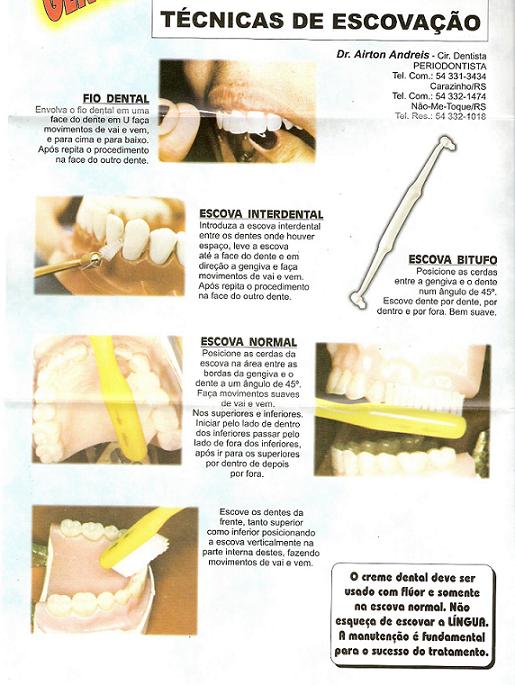

Medidas preventivas visando a remoção da placa e prevenindo sua recorrência, pode ser conseguido tanto mecânica(escovação) como quimicamente(bochechos); algumas vezes os dois procedimentos são combinados.

O controle da placa envolve o trabalho profissional e os cuidados de casa; estes constituem-se pela soma dos efeitos de motivação, conhecimento, instrução em higiene oral, elementos auxiliares de higiene oral e habilidade motoras.

A combinação de instrução de higiene oral e a limpeza mecânica profissional dos dentes a intervalos adequados pode, quase completamente, prevenir o desenvolvimento de ambos, gengivite e periodontite.(Axelsson, P.)

O paciente com doença periodontal deve seguir um controle de escovação adequado, como mostra o quadro a seguir.